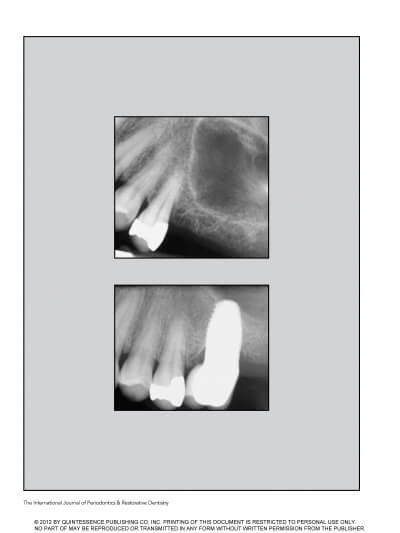

MAXILLARY SINUS AUGMENTATION- 3 CASES

SINUS FLOOR AUGMENTATION WITH HYDROPNEUMATIC TECHNIQUE

SINUS AUGMENTATION PROCEDURES